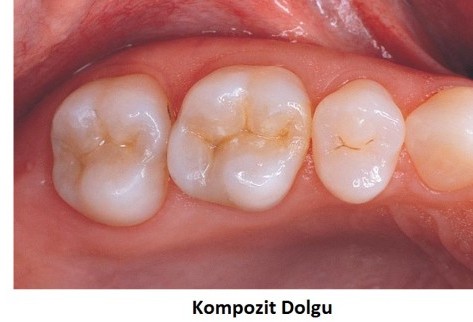

Restoratif Tedavi

Çürük, kırık ve aşınmış dişlerin estetik dolgular ve kaplamalarla onarımı.